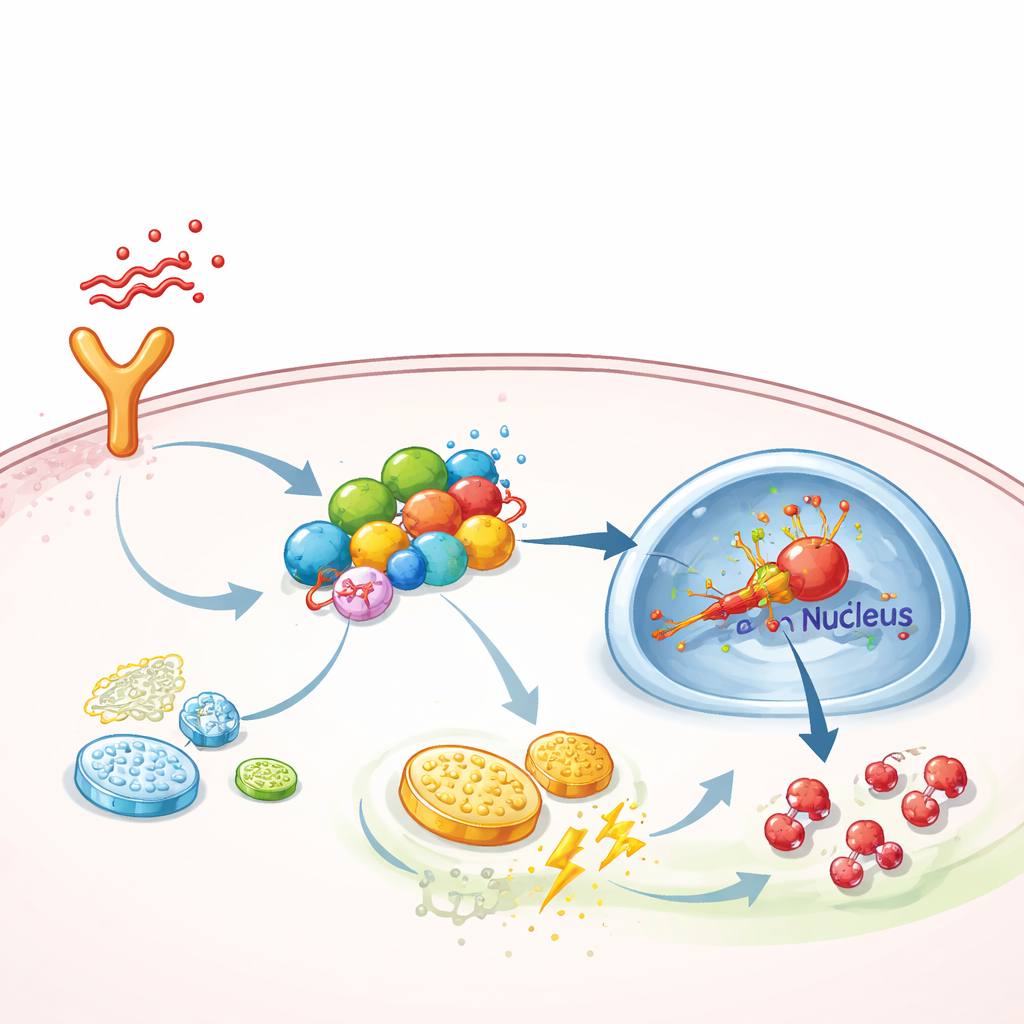

Approfondendo i meccanismi, il team ha indagato come FGF13 spinga le cellule verso questo metabolismo ad alto regime. Hanno scoperto che FGF13 si lega fisicamente a diversi proteine di segnalazione che formano una catena dai recettori di superficie fino al nucleo cellulare—specificamente il percorso TAK1–MEK–ERK, noto per attivare un regolatore principale delle risposte a basso ossigeno chiamato HIF-1α. FGF13 agisce come uno scaffold, mantenendo questi componenti insieme in modo che i segnali viaggino più efficacemente. Quando FGF13 veniva ridotto, l’attivazione di ERK e HIF-1α diminuiva e la glicolisi si affievoliva; quando FGF13 era aumentato, la via diventava iperattiva. La sovraespressione di HIF-1α nei topi annullò il beneficio protettivo dell’eliminazione di FGF13, mentre un inibitore selettivo di ERK, SCH772984, neutralizzò il danno causato dalla sovrapproduzione di FGF13 e migliorò le condizioni polmonari negli animali settici.